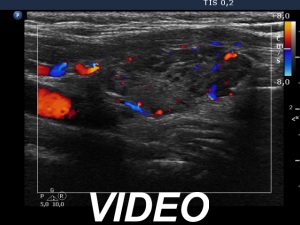

Ultrasound. The thyroid has echonormal and hypoechoic areas. The echogenicity index was greater than 50%. There was a relatively larger echonormal areas in the central-dorsal part of the left lobe. This was less influenced by the underlying thyroiditis. Nevertheless, neither this nor other areas in the thyroid corresponded to true nodules. the so-called honeycombing pattern, i.e., there were numerous small hypoechogenic areas within an echonormal background. The largest hypoechogenic area was misinterpreted as a nodule on previous ultrasound examination. This field was simply the largest of the similarly hypoechogenic parts of the thyroid. Considering the body mass, the thyroid was not enlarged.